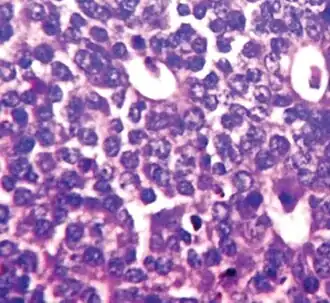

Nuclear pleomorphism

This parameter assesses whether the cell nuclei are uniform like those in normal breast duct epithelial cells, or whether they are larger, darker, or irregular (pleomorphic). In cancer, the mechanisms that control genes and chromosomes in the nucleus break down, and irregular nuclei and pleomorphic changes are signs of abnormal cell reproduction.

Note: The cancer areas having cells with the greatest cellular abnormalities should be evaluated.

- 1 point: nuclei with minimal or mild variation in size and shape

- 2 points: nuclei with moderate variation in size and shape

- 3 points: nuclei with marked variation in size and shape

Invasive ductal carcinoma with marked nuclear pleomorphism.

Invasive ductal carcinoma with marked nuclear pleomorphism.